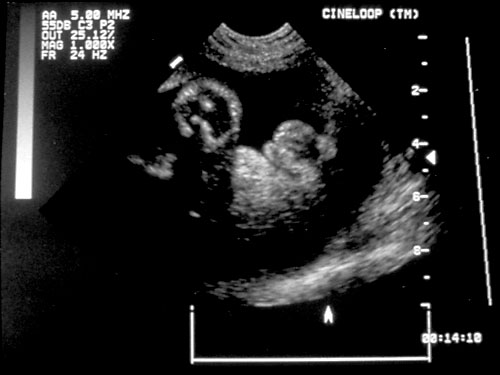

Normal cervical spine at 18 weeks (1). Another normal sagittal view of cervical spine seen in third trimester with folds of fat seen (2). Normal thoracic spine at 18 weeks (3). Normal sagittal view of lumbosacral spine at 18 weeks (4). Normal transverse view of lumbosacral spine at 18 weeks (5). - Extremities (hands/feet)

Normal fetal hand with four fingers and thumb on right side of photo (left). Normal fetal feet with five digits on each with normal anatomy (right).- Femur length — accurate for measuring gestational age.